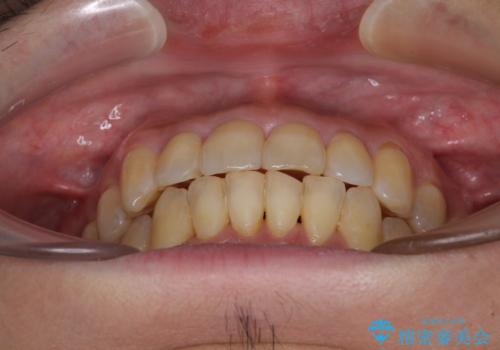

前歯のデコボコ ワイヤー装置での短期間治療

- 前歯のデコボコを気にして来院された患者様です。

インビザラインまたはワイヤー装置、どちらでも対応可能でしたが、自己管理の少なさ、期間の短さから、ワイヤー装置による矯正治療を行うこととしました。

治療開始の頃は、食事や歯磨きが慣れず、装置が頻繁に脱落しましたが、2,3ヶ月ほどで慣れ、その後は1年ほどで治療を終えることができました。